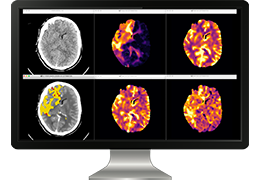

成像智能。

Eclipse 成像智能功能提供强大的处理能力和最佳质量的影像,同时减少质量错误并提高剂量效率。

凭借 AI、专有算法和先进的影像处理能力,提供出色的影像质量和无与伦比的诊断信心。

与标准影像处理相比,智能降噪功能可使客户降低辐射剂量,而不会损失影像质量。这在新生儿和儿科成像中尤其重要,在这种情况下以尽可能低的剂量成像至关重要。

提供相配视图选项,以减少所需的曝光次数,并提供更清晰的感兴趣区域视图。